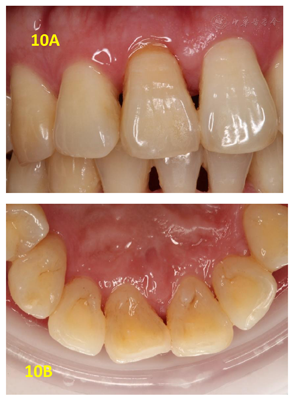

翻瓣探查术后3个月复查(2018年2月28日):检查:11舌侧暂封在,叩痛(-),Ⅰ-松动,唇侧龈退缩3 mm,牙龈充血,近中唇侧位点PD5 mm,余位点2~3 mm,见图6。X线片示:11近中骨质吸收已大部分恢复,见图7A。处置:11上橡皮障,3%次氯酸钠+生理盐水冲洗,干燥,Iroot SP+牙胶尖根充完成根管治疗见图7B,酸蚀粘接,树脂充填,调

11根管充填后3个月、半年、四年半复查,11均无不适,叩痛(-),不松,牙龈未见明显红肿等,PD 2~4 mm。x线片均显示11近中骨质恢复良好。在随访的四年半,牙周维护依靠患者自行的口腔卫生维护,均未再进行任何牙周治疗。